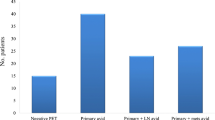

Simple risk stratification using FDG-avid nodes after NAC, and an impassable tumour

As the presence of avid nodes after NAC and/or an impassable tumour before appeared the most reliable predictors of incurable disease at surgery, three risk groups were derived: low (neither factor; n = 181), medium (one; n = 58) and high (both; n = 8). The risk of incurable disease increased dramatically: low (7/181; 3.87 %), medium (13/58; 22.4 %), and high (6/8; 75.0 %; (p < 0.001, Fisher’s exact test)